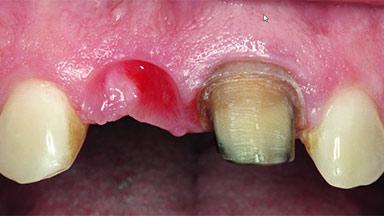

Replacement of a Missing Upper Left Central Incisor, Late Placement of an RC Bone Level Implant and Adjacent Tooth Restoration

A healthy 38-year-old male patient was referred for replacement of a failing tooth-supported cantilever fixed dental prosthesis on teeth 11 and 21. The patient reported a history of trauma at 13 years of age that had resulted in the subsequent loss of tooth 11, as well as endodontic treatment of the adjacent abutment tooth 21. A metal-ceramic cantilever fixed dental prosthesis replacing tooth 11 had been provided by his general dentist several years after the loss of the tooth, with tooth 21 as the sole abutment. At the time of initial presentation, this restoration had been in service for over 20 years.